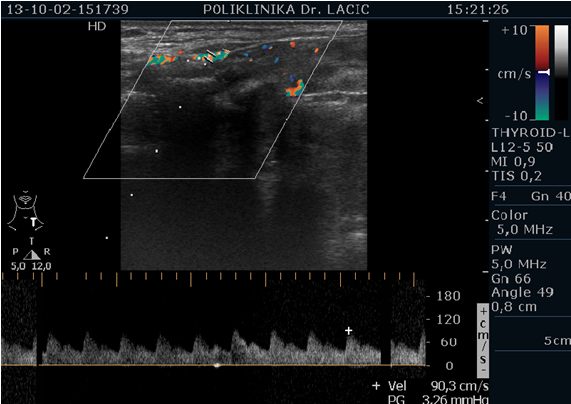

Color Doppler je temeljen na ultrazvučnoj tehnologiji koja pomoću Doppler-ovog efekta procjenjuje prokrvljenost cijele štitnjače i čvorova u štitnjači, kao i limfnih čvorova vrata. Pomoću color Dopplera računamo brzine protoka kroz krvne žile koje hrane štitnjaču, čime dobivamo važne hemodinamske parametre. Na temelju ovih pokazatelja donosimo važne dijagnostičke zaključke, te efikasno pratimo efekte liječenja štitnjače.

U sklopu Centra za štitnjaču Poliklinike Lacić nabavljen je najnoviji američki ultrazvučni aparat sa color Dopplerom Philips Affiniti 70, koji je opremljen jedinstvenim „PureWave“ ultrazvučnim sondama. Tehnologija izrade tzv. „single crystal“ ili „PureWave“ ultrazvučnih sondi omogućuje duboku penetraciju što omogućuje bolju vizualizaciju štitnjače i svih struktura vrata. Philips Affiniti 70 ultrazvučni sustav je jedini sustav u klasi koji može koristiti „single crystal“ ili „PureWave“ tehnologiju. Čisti, uniformni „PureWave“ kristali imaju 85% bolju učinkovitost prilikom emitiranja i primanja ultrazvučnih zraka nego klasični piezoelektrični materijali. Ova izuzetna tehnologija omogućuje naprednu penetraciju uz izvrsnu rezoluciju u dubljim dijelovima slike, čime se postiže vrhunski prikaz štitnjače i svih struktura vrata. Time se omogućuje još točnije mjerenje svih morfoloških kao i hemodinamskih parametara. Na taj način smo u mogućnosti još ranije otkrivati bolesti štitnjače a samim time ih onda i bolje liječiti.